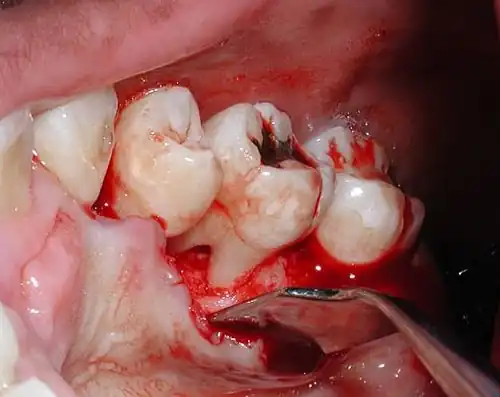

Evidence of furcal bone loss on #18 (lower left permanent second molar), along with a mesial vertical defect on the same tooth. The bent "stick" on the left of the tooth is a piece of gutta percha being used to trace the defect.

Bone loss from aggressive periodontitis that led to an exposed furcation on an upper molar. In health, the bone exists about a millimeter and a half away from the cementoenamel junction, which is the line that separates the crown from the root trunk (the line can be seen clearly in the photo).